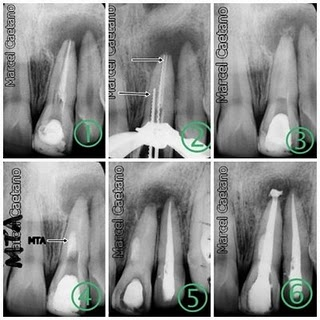

Muitas vezes são realizadas retrobturações, ou seja, tampa-se o ápice dental com um material especial a fim de promover um melhor selamento no fim do canal.Se diagnosticado cedo, o tratamento é rápido e com poucas sequelas.

Caso Clinico

Paciente apresentou-se com lesão periapical veja RX inicial, foi indicada a cirurgia e no ato foi retirado material para exame histopatologico, para se descobrir a natureza da lesão.